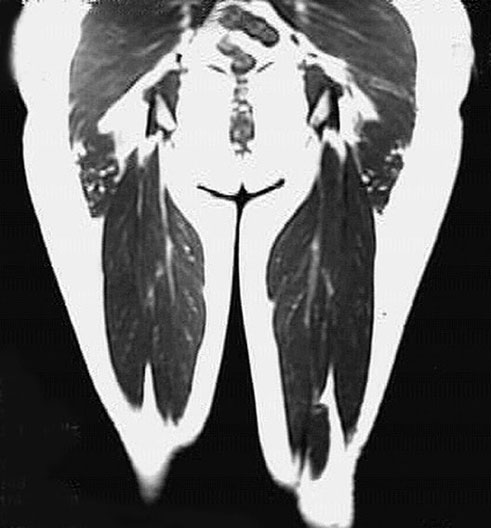

Thigh Coronal View

*No labels on this image